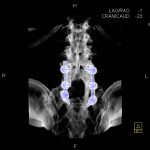

- Diagnosticul fracturilor:

-

- Unice

- Multiple

- Cu înfundare

- Complexe cranio-sinusale

- Complexe cranio-etmoidale

- Complexe cranio-orbitare

- Complexe cranio-faciale